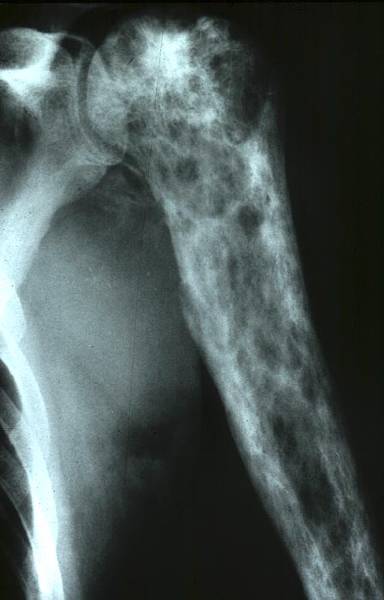

Tumeur osseuse visiblement maligne: quel est le diagnostic probable?

Lésion épiphysaire à matrice cartilagineuse (pop corn) d’allure maligne = Chondrosarcome de l’humérus